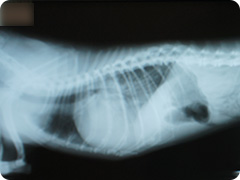

- 肺水腫

- 犬では僧房弁閉鎖不全などの心不全から肺水腫を起こし、呼吸が早くなったり咳が出たりします。

-

肺水腫

胸腔内が白っぽく見えます。心臓の超音波検査を行い診断します。

超音波検査

左心房と左心室の間にある僧房弁が閉じないので血液の逆流が見られ、超音波検査ではモザイク状に見えます。

肺水腫治療後

心不全の治療により肺水腫は改善し、胸腔内は黒っぽく見えるようになりました。 -